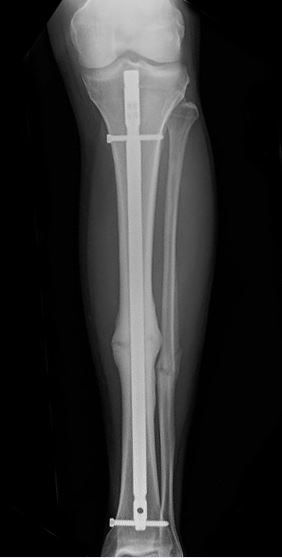

Shinbone fracture treated with intramedullary nailing

This X-ray shows a healed shinbone fracture treated with intramedullary nailing.